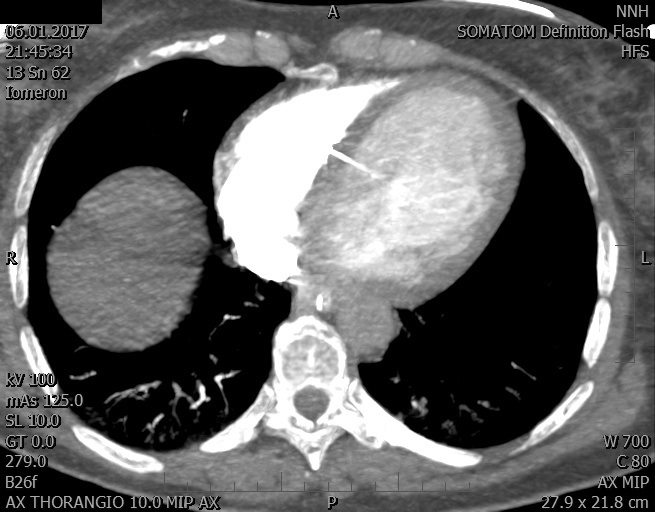

Video 2 - Echokardiograficky byla zjištěna těžká dysfunkce dilatační levé komory s nezvětšenou pravou komorou.Pro nejasnou příčinu zástavy jsme provedli i vyšetření výpočetní tomografií (CT), které vyloučilo plicní embolizaci (série 1 - soubory na konci článku). V den přijetí při přetrvávající oběhové nestabilitě byla nemocná opakovaně defibrilována pro fibrilaci komor se stabilizací rytmu po podání amiodaronu a mesocainu. Dle hemodynamických měření se jednalo o těžký kombinovaný šok. Vstupní laboratorní vyšetření bylo bez větších pozoruhodností. Posléze jsme doplnili anamnézu od příbuzných a zjistili, že pacientka užila do dvou hodin před srdeční zástavou první tabletu amoxicilinu na lehký respirační infekt. Při nevýtěžnosti vstupních vyšetření a nových anamnestických informacích jsme doplnili 14 hodin po kolapsu vyšetření koncentrace tryptázy v séru, která byla extrémně zvýšena (tabulka 2), což nás vedlo k podezření na anafylaxi.